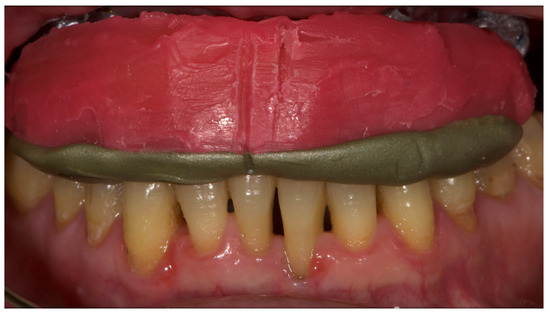

Figure 3.

The internal part of the prosthetic restoration, the one in contact with the mucosa, shows the incorrect shape of the pink flange, which leads to the accumulation of plaque and food.